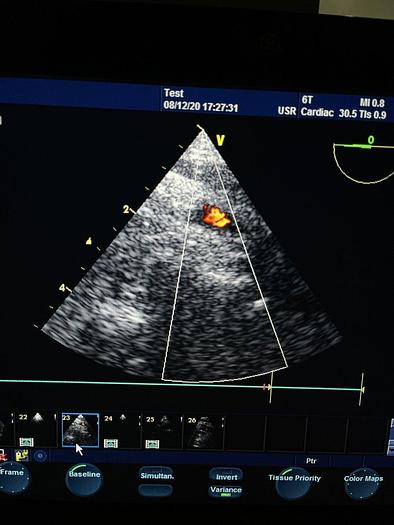

| Hersteller | GE Medical System |

| Modell | 6T |